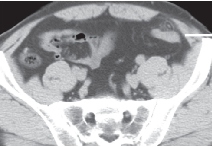

最后,做了腹盆增强CT。典型的男图像介绍如下:

上面4图分别为:平扫鼓像、动脉有啥期、门脉期、延迟期

影像表现:于升结肠前方可见一不规则团块状脂肪密度影,周围怀孕脂肪密度增高,升结肠周围可见饱满淋巴结,邻近肠壁有轻微增厚,无明显脓肿及肠梗阻征象。

诊断:升结肠肠脂垂炎在什么。